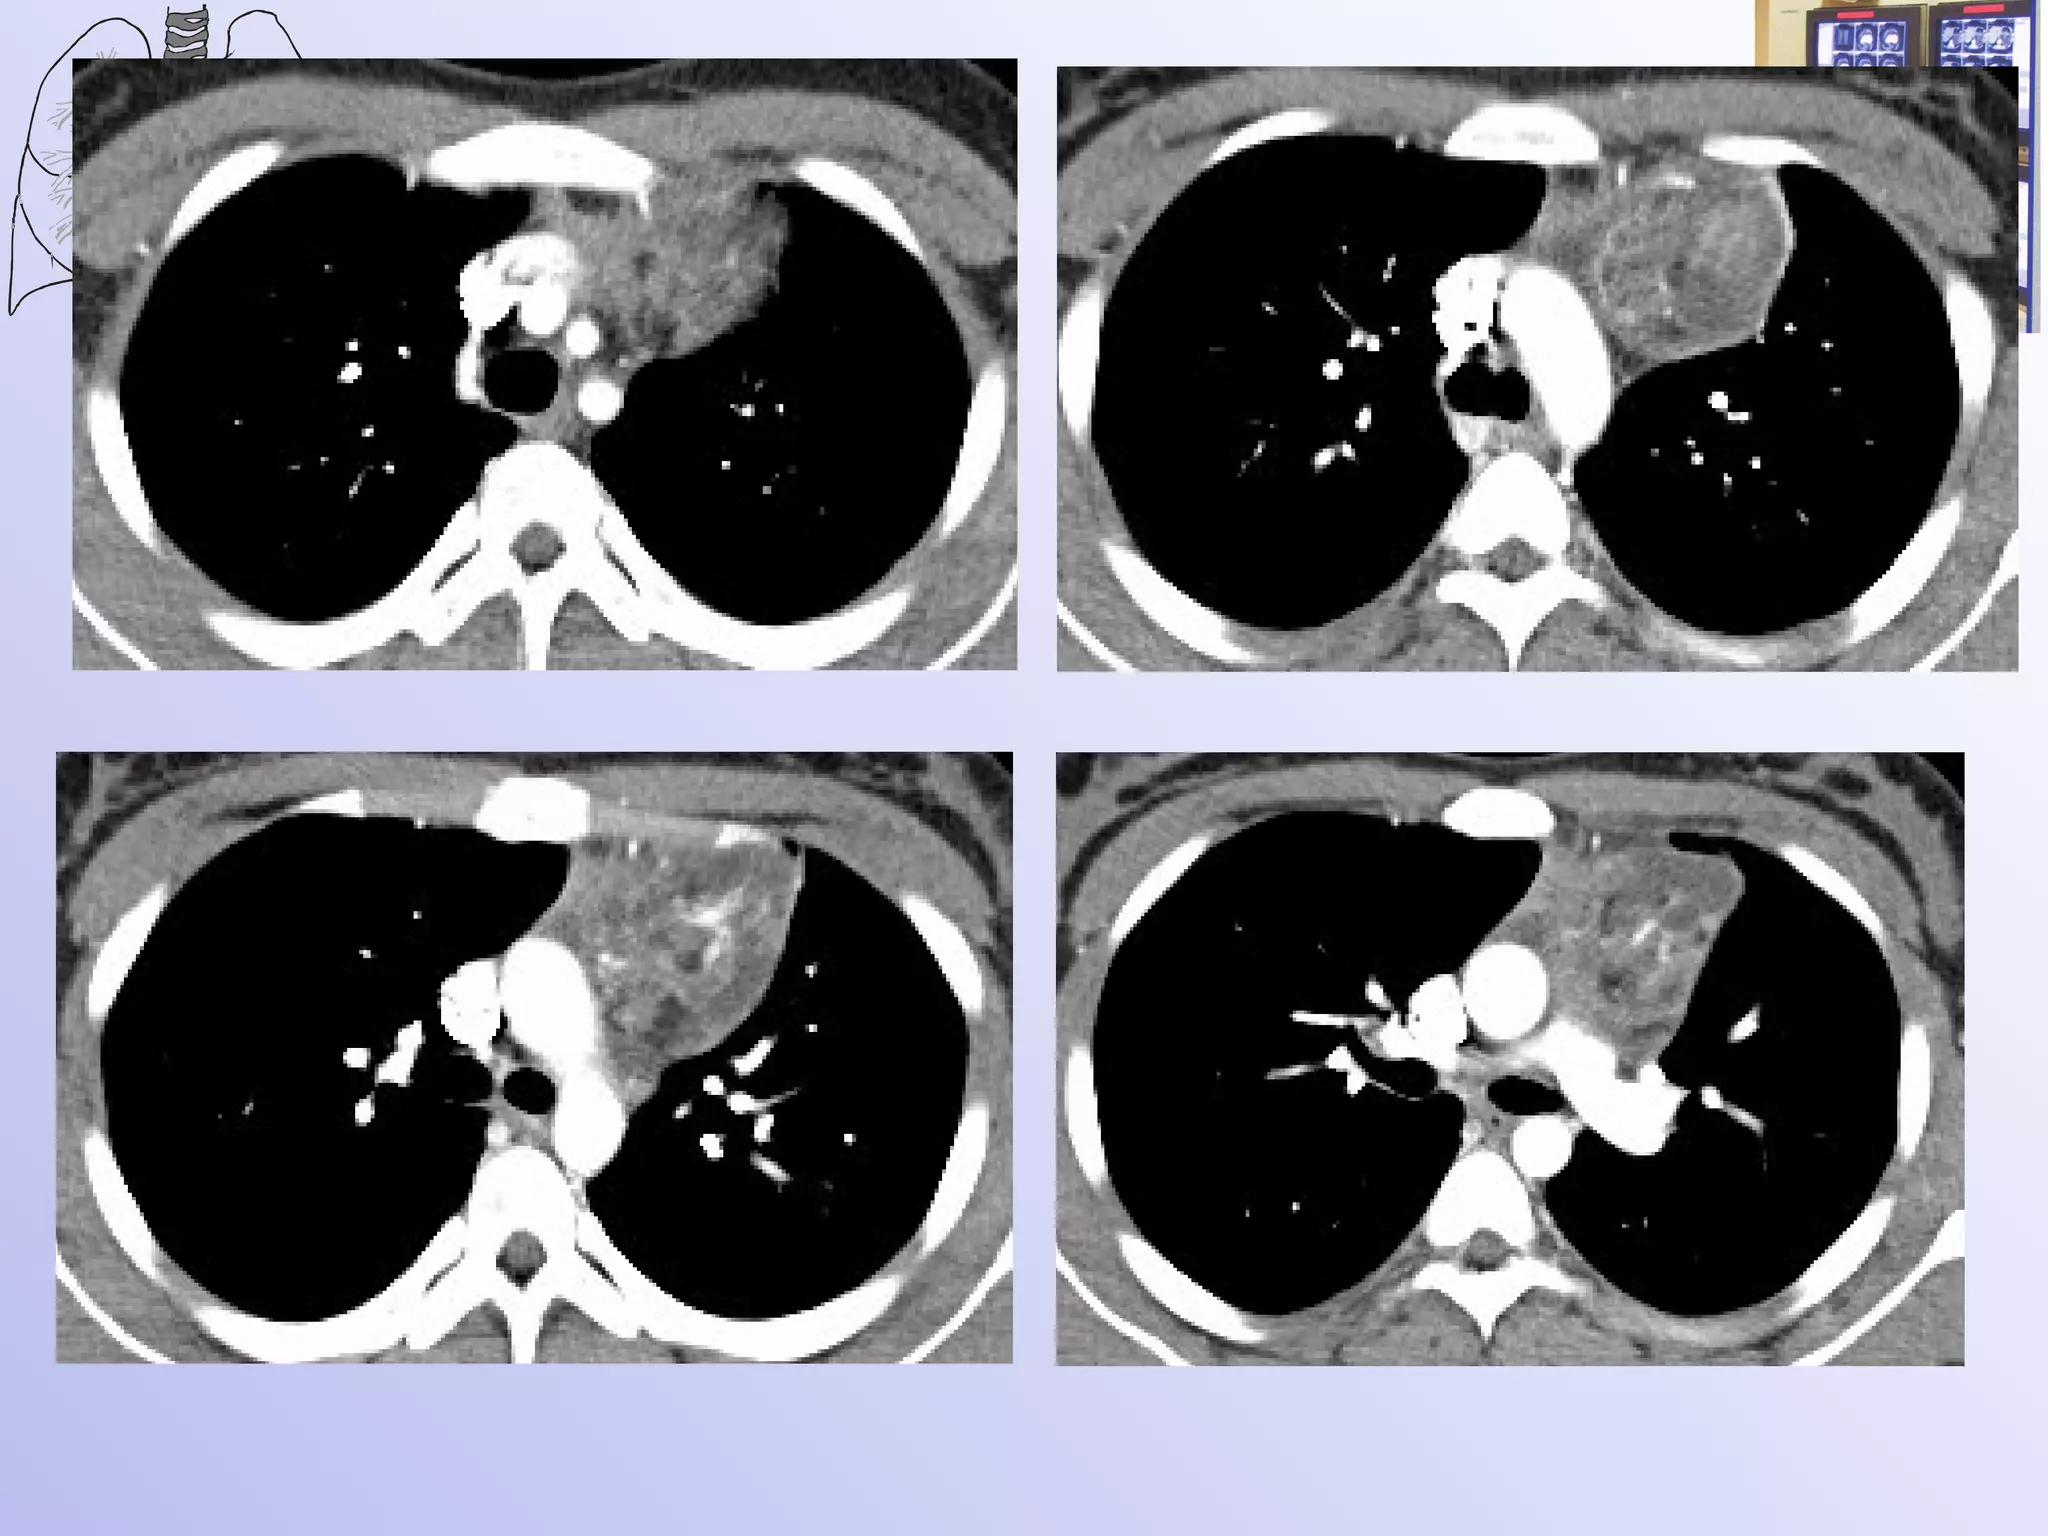

Рентгенологическая и КТ семиотика злокачественных тимом Чаще двустороннее, но м.б. и одностороннее расположение Поверхность бугристая, контуры нечеткие При инфильтративном росте прорастает в плевру и легкие, реже в грудину и грудную стенку спереди При больших размерах может сдавливать трахею и крупные сосуды, редко их прорастает Структура опухоли неоднородна, видны очаги распада

Злокачественная тимома

Рентгенологическая и КТсемиотика злокачественных тимом Чаще двустороннее, но м.б. и одностороннее расположение Поверхность бугристая, контуры нечеткие При инфильтративном росте прорастает в плевру и легкие, реже в грудину и грудную стенку спереди При больших размерах может сдавливать трахею и крупные сосуды, редко их прорастает Структура опухоли неоднородна, видны очаги распада

• 14.